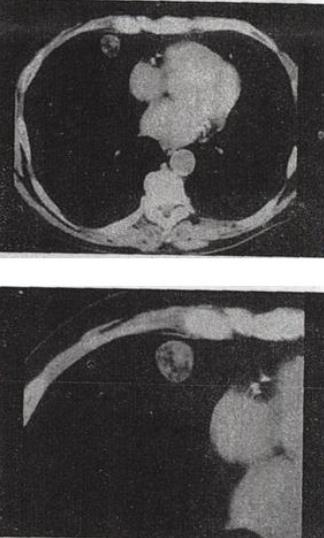

患者女,71岁,咳嗽,咳痰,胸部隐痛2个月余,结合影像学检查,最可能的诊断是()。

A:肺癌

B:肺结核

C:肺错构瘤

D:结节病

E:肺转移瘤